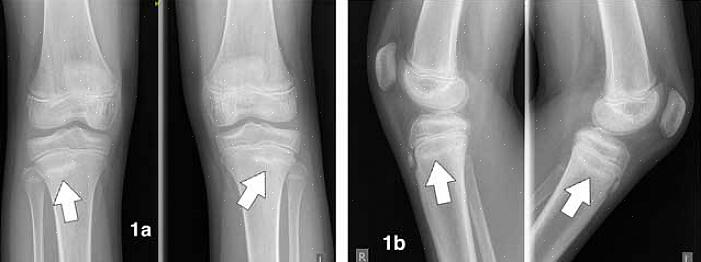

תסמינים של שברי מאמץ בטיביה

שברי מאמץ בטיביה שכיחים למדי. השרירים בחלק הקדמי של הרגל בדרך כלל לא עובדים הרבה, ובמקום זאת, אנו מעדיפים את הגב. המשמעות היא שהשריר בגב מושך את השוקה ללא כל התנגדות. לפיכך, הסיכון שלך לשברי מאמץ באזור זה עולה במידה ניכרת.

בשלבים הראשונים של שבר מאמץ, תבחין באי נוחות קלה בלבד באזור השוק. אי הנוחות הזו תיעלם בזמן מנוחה.

לאחר מכן, אותו כאב מקומי ילך רחוק יותר, ותתחיל לשים לב שהאזור דלקתי: נפוח, אדום וחם. אתה עשוי גם להתחיל להבחין בכאב בלילה, והאזור הפגוע יהיה רגיש מאוד למגע או להלם.

לא יהיו תסמינים נוספים של שבר מאמץ. בגלל זה, קבלת אבחנה מדויקת יכולה להיות מסובכת. רופא ישלול מצבים אחרים כגון בעיות גידים, פריוסטיטיס ותסמונת קומפרטמנט, בין היתר. לכן, חשוב לפנות לרופא שיבצע את הבדיקות הנדרשות וימצא אבחנה מוצלחת.